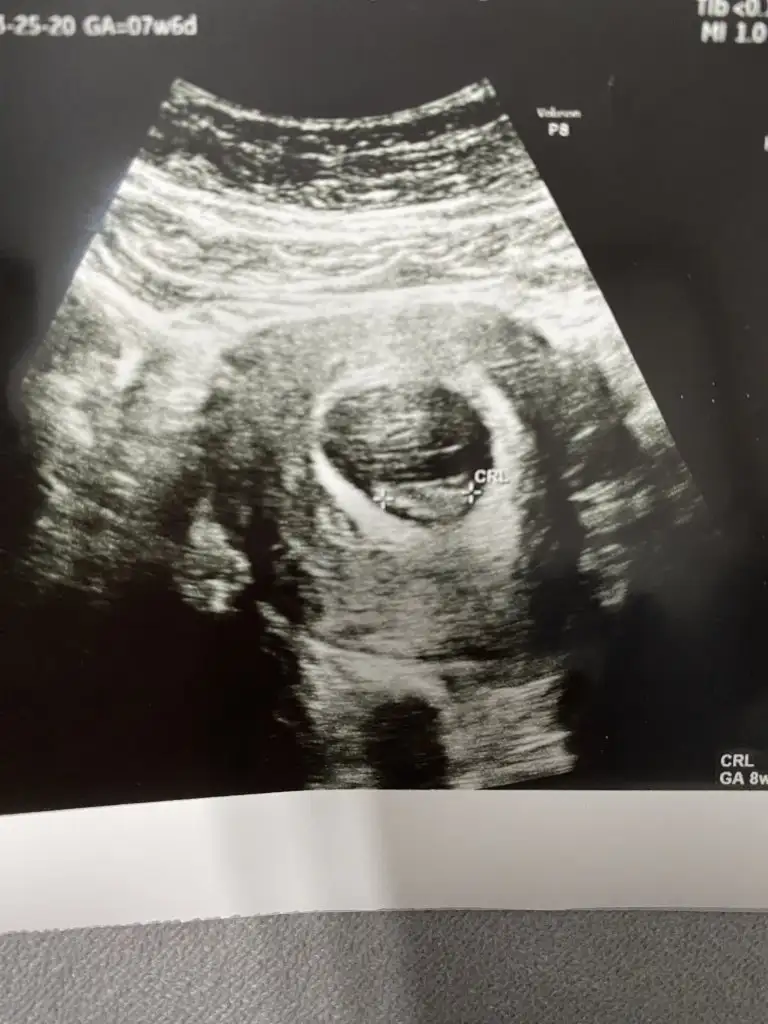

Merhaba lütfen bana da bakabilir misiniz 7 hafta 6 günlük karından ultrason

• IMG_1055.webp

• IMG_1056.webp